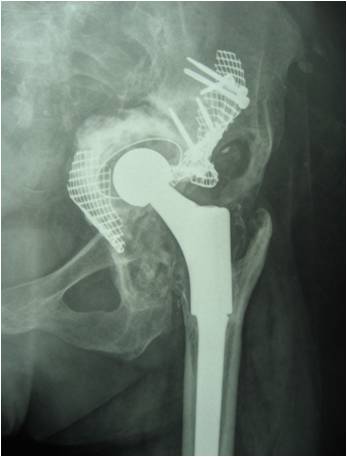

19髋中,18髋的髋臼假体稳定,未发现臼杯在垂直和水平方向大于1mm的移位,也未发现髋臼假体外展角的改变(图1-3)。有1例PaproskyⅢB型患者出现金属网及髋臼杯明显移位等影像学松动表现:术后12月随访时,髋臼上移16.8mm,内移4.7mm;术后28月时,髋臼上移22.7mm,内移5.8mm,髋臼假体外展角较术后减小2.2°(图4-6)。但患者髋关节疼痛不明显,日常生活中能无需手杖独立行走,拒绝再次翻修手术。

图1 全髋关节置换术后无菌松动,髋臼PaproskyⅢA型骨缺损

图2 术后6周,臼底缺损用金属网封闭

图3 术后36月 异体骨整合良好

图 4 全髋关节置换术后无菌松动,髋臼PaproskyⅢB型骨缺损

图 5 术后X片见臼底骨折,骨缺损未完全封闭

图 6 术后28月植骨层后连续性放射学透亮线,髋臼假体明显上移松动